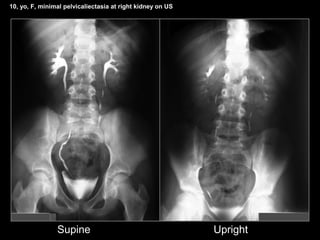

4. Emptying of collecting sistem

51 patients (31%)

10, yo, F, minimal pelvicaliectasia at right kidney on US

Supine Upright